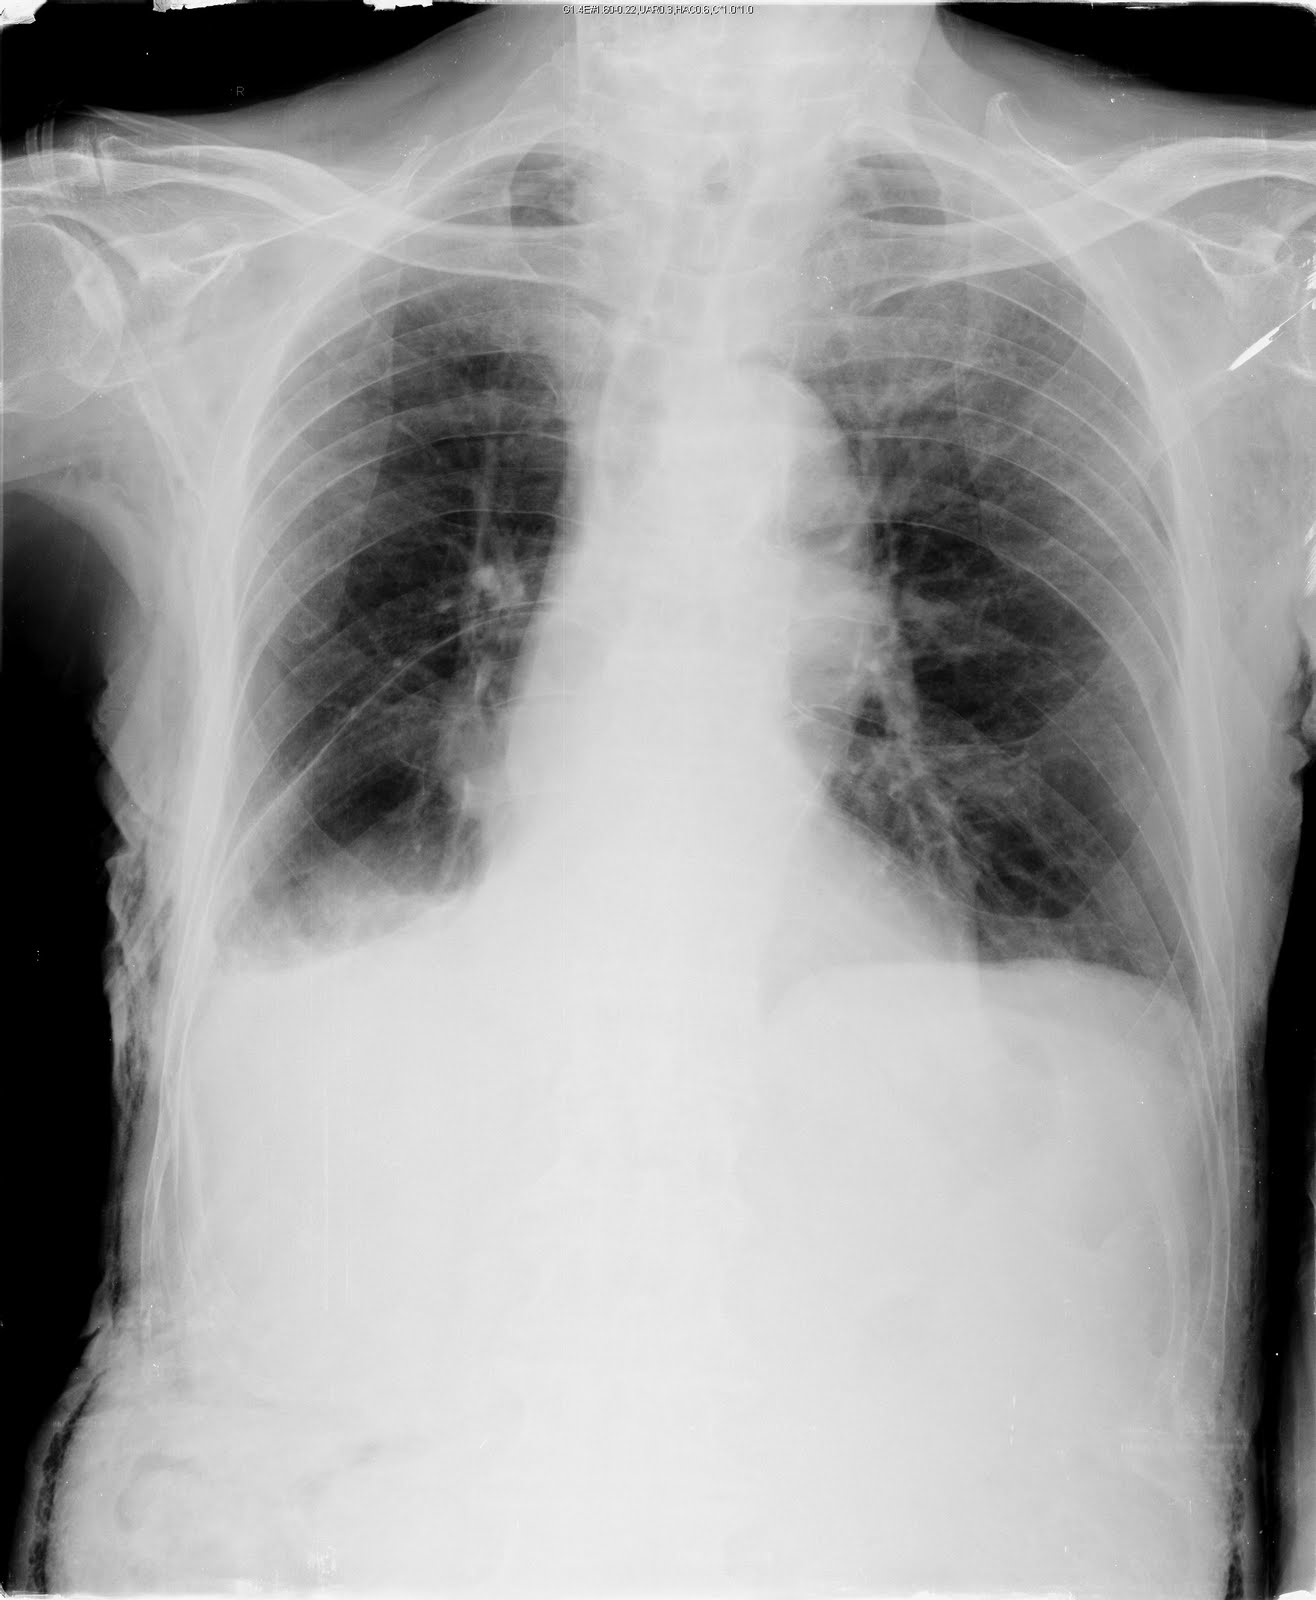

Interdependence in the lung

如上圖,88M, COPD with right pneumothorax history. Chest tightness for hours, HR120 beats/min, RR 32/min, BP 137/65 mmHg. PE: RLL decreased breath sound. EKG: RBBB pattern, no significant STT changes. Give O2 non-rebreathing mask 100% and oximeter showed SpO2 89%.

CK-MB, troponin-I normal limit.

Favor chest tightness due to interdependence in the lung (personal opinion)